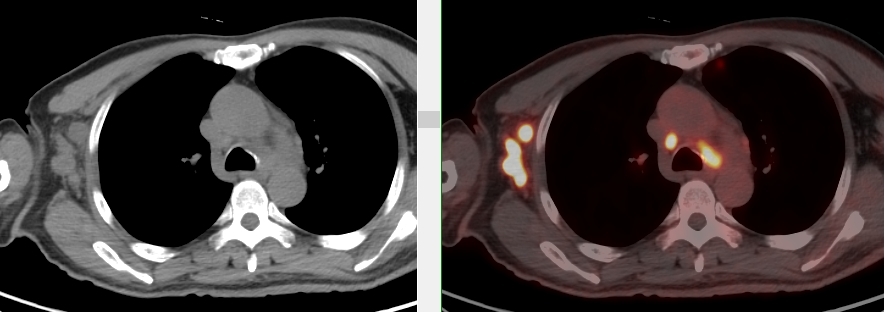

頸胸部多處代謝異常病灶

完善胸部強化CT考慮縱隔MT并縱隔、右腋窩及雙肺門多發(fā)腫大淋巴結,后行超聲引導下行右腋窩腫物穿刺活檢術,病理首先考慮惡性腫瘤,因穿刺組織局限,腫瘤細胞成分過少,不能明確診斷。

完善PET/CT檢查示:右側腋窩、雙側中下頸部、縱隔、雙側肺門多發(fā)MT,建議淋巴結活檢。后患者行右腋窩淋巴結切除活檢術,經北京大學第三醫(yī)院病理科會診示:右腋窩淋巴結惡性腫瘤,呈淋巴竇內生長模式,瘤細胞呈上皮樣,異型性明顯,伴中性粒細胞浸潤。結合病史及免疫組化,考慮為SMARCA4(BRG1)缺失的胸部腫瘤,伴神經內分泌標記表達。

本例為罕見病理類型的腫瘤,影像學表現無明顯特異性,診斷困難。強化CT和穿刺病理已基本明確為惡性腫瘤,行PET/CT檢查一是為了全身檢查,完善分期,二是根據PET代謝情況指導進行生物靶區(qū)活檢,進一步明確病理診斷。最終,PET/CT除縱隔病變外發(fā)現更多頸胸部淋巴結代謝異常,綜合考慮后對腋窩淋巴結進行切除活檢,最終得到病理證實。